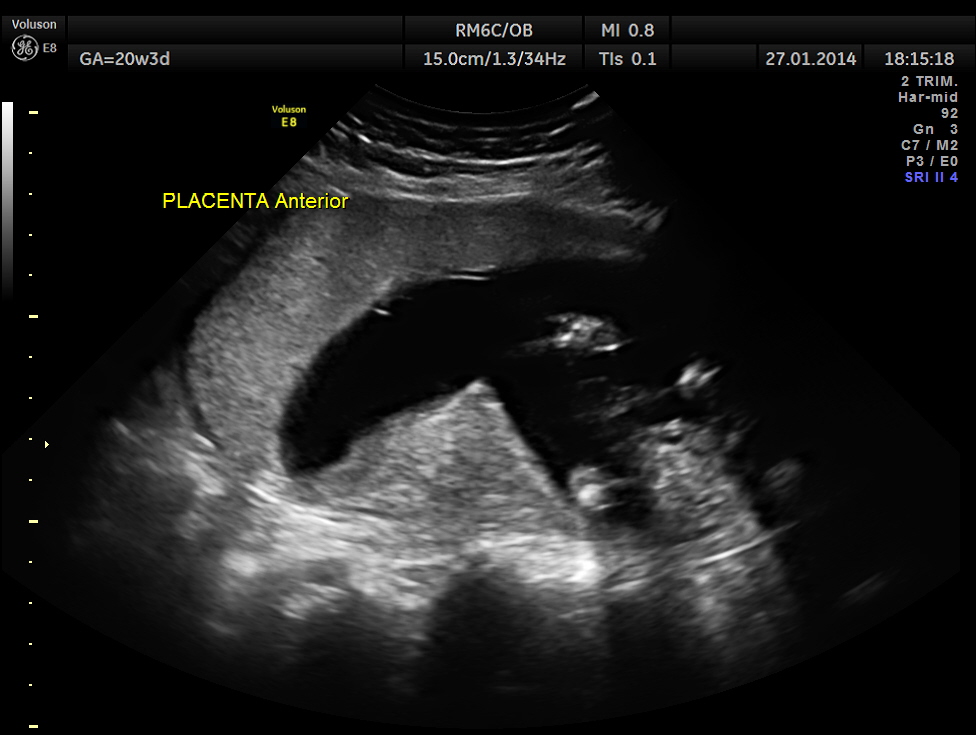

The GA was around 25 weeks , but the AUA was around 19 to 20 weeks. All parameters – BPD, HC, AC, FL are < 2.3 %tile and all other long bones are < 5.0 %tile.

Prominent placentomegaly seen .

Oligohydramnios seen.

Fetal kidneys are hyperechoic and enlarged.

Umbilical arterial P.I. and R.I. are higher for the GA.

At this point a diagnosis of Placentomegaly , Symmetrical Intra Uterine Growth Restriction , Probable renal dysplasia with oligohydramnios was suggested . The patient was referred by her consultant to a higher centre . The patient opted for termination of pregnancy as the 2nd opinion was also not favourable. But she had a spontaneous abortion few hours before the planned procedure. The fetus and the placenta underwent autopsy . The findings are summarised below :

Please look at the placenta again . The infarcts are made out clearly.